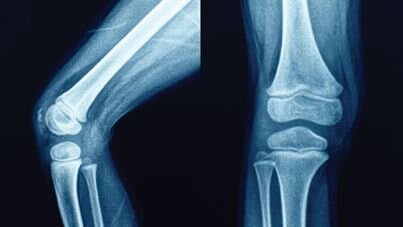

Хруст в суставах – щелчки или легкий треск, который возникает при сгибании или растягивании сустава. Ярким примером могут служить щелчки пальцами – такое явление характерно для большинства суставов. Щелчки...

Почему щелкают суставы и хрустят кости? Это нормально или нужно показаться врачу? Разбираемся 🤫 Хруст в суставах — распространённый симптом, который встречается у большинства людей, и в большинстве случаев это не представляет опасности. Тем не менее, есть сигналы, на которые стоит обратить внимание: ▫️ боль в суставе; ▫️ припухлость и отёчность вокруг сустава; ▫️ покраснение кожи...